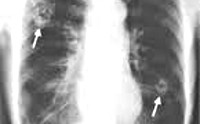

B66.4 Парагонимоз